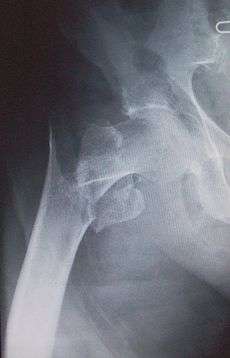

Intracapsular fractures

For low-grade fractures (Garden types 1 and 2), standard treatment is fixation of the fracture in situ with screws or a sliding screw/plate device. This treatment can also be offered for displaced fractures after the fracture has been reduced...

In elderly patients with displaced or intracapsular fractures many surgeons prefer to undertake a hemiarthroplasty, replacing the broken part of the bone with a metal implant. The advantage is that the patient can mobilize without having to wait for healing.

In elderly patients who are medically well and still active, a total hip replacement may be indicated.

Traction is contraindicated in femoral neck fractures due to it affecting blood flow to the head of the femur.[12]